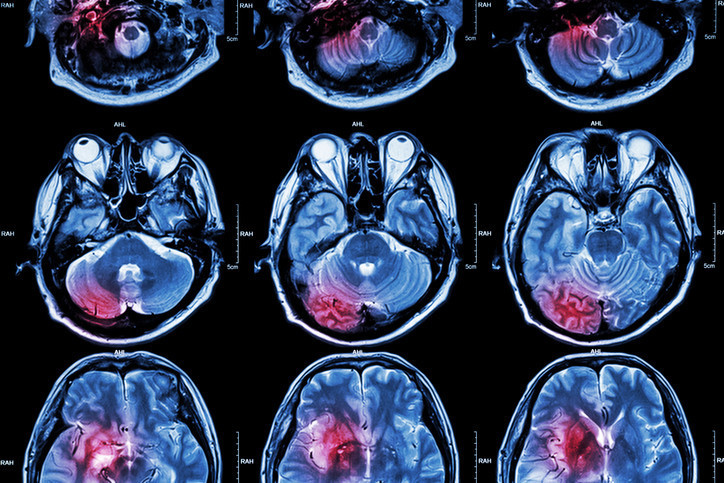

Eşi Bev Hill, ameliyattan sonra eşini gördüğünde konuşamadığını ve bunun kendisi için son derece sarsıcı bir an olduğunu anlattı. İlk değerlendirmelerde bu durumun ameliyat sonrası oluşan olağan şişlikten kaynaklanabileceği düşünüldü. Ancak daha sonra çekilen MR görüntülemesinde gerçeğin farklı olduğu anlaşıldı.

Stuart Hill’in felç geçirdiği ortaya çıktı. Felcin, beynin konuşma ve dil işlevlerini yöneten bölgesini etkilediği belirtildi. Aradan yaklaşık 10 ay geçmesine rağmen Hill’in hâlâ konuşma konusunda güçlük yaşadığı, kelimeleri toparlamakta zorlandığı ifade edildi. Bununla da sınırlı kalmayan süreçte bir nöbet geçirdiği ve bu nedenle artık her gün 2 kez nöbet önleyici ilaç kullandığı açıklandı.